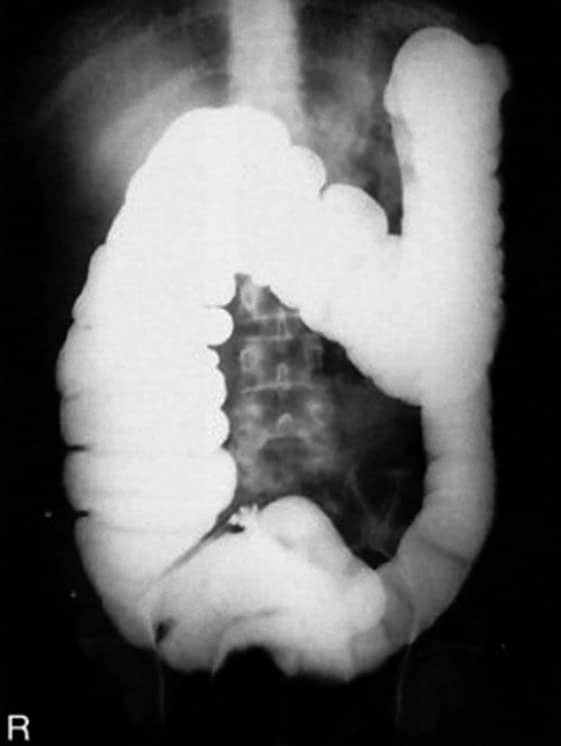

Incidência PA ou AP – Enema baritado

PA de enema baritado ou AP em destaque (foto menor).

Justificativa para realização do exame

Visualizar obstruções, incluindo íleo paralítico, volvo e intussuscepção.

Principais estruturas demonstradas

Todo o intestino grosso, com algumas exceções na ausência do reto na imagem, que pode ser realizado em um estudo à parte em um filme menor, geralmente o 24x30cm, se houver necessidade e a critério clínico.

Fatores técnicos e posicionamento

• DFF: 1m.

• Tamanho do filme/receptor de imagem e sentido: 35x43cm no sentido longitudinal.

• Técnica de referência: 4mAs e 125KV, na mesa.

• RC: perpendicular no centro do filme e ao nível das cristas ilíacas.

• Posição do paciente e da parte ou região do corpo: paciente em decúbito ventral, com os braços para cima, fornecendo um travesseiro para o rosto, que deve ficar de lado, bem acomodado.

• Respiração: parar a respiração e expor durante e expiração lenta.